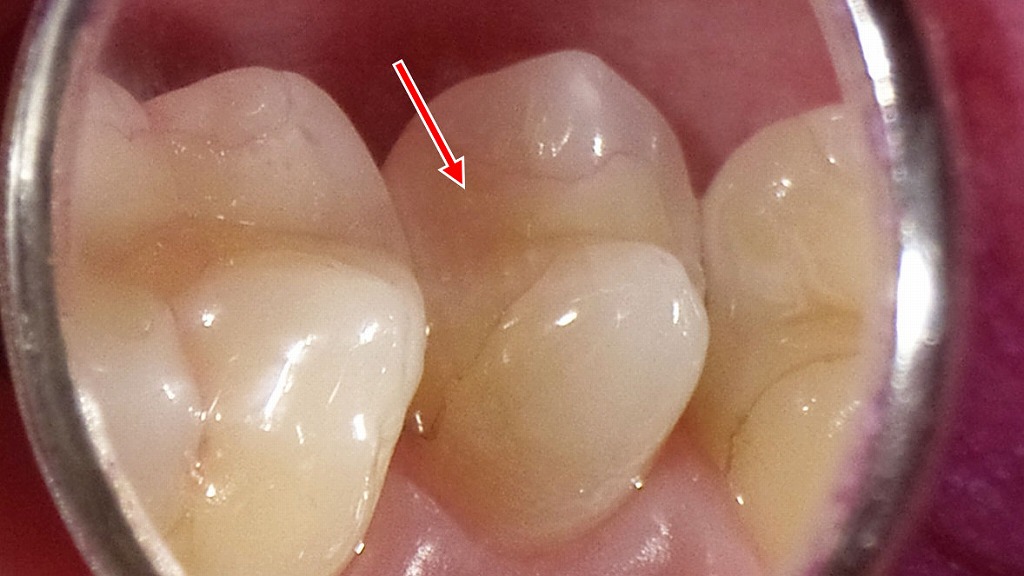

🎨インレーの見た目

保険適用メタルインレー

上顎小臼歯2本と第一大臼歯に保険適用インレーの金パラインレーが入っています。